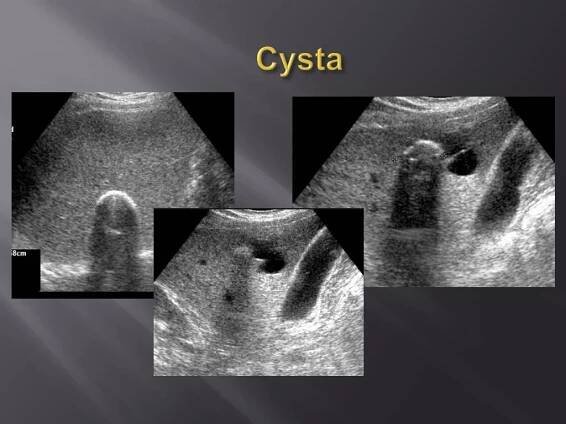

Benigní ložiskové léze jater